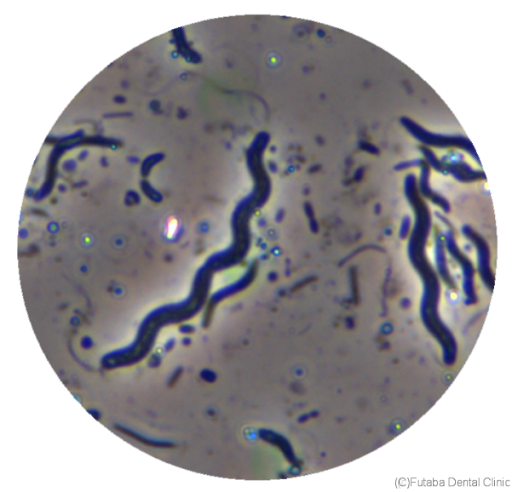

トレポネーマ

らせん状の菌で、顕微鏡で容易に観察されやすい歯周病菌です。一番わかりやすく、この菌が多く存在して元気に活動しているようなら歯周病対策をしっかり行う有力な指標となります。

グラム陰性嫌気性菌で、運動性が高くらせん状をしており、スピロヘータ属にはいります。

免疫反応を制御して炎症の慢性化に関与する、たいへん厄介な細菌です。

難治性の歯周病患者で、歯肉から排膿しているところに必ず存在していて、人の腸管や泌尿・生殖器表面等全身から検出されます。